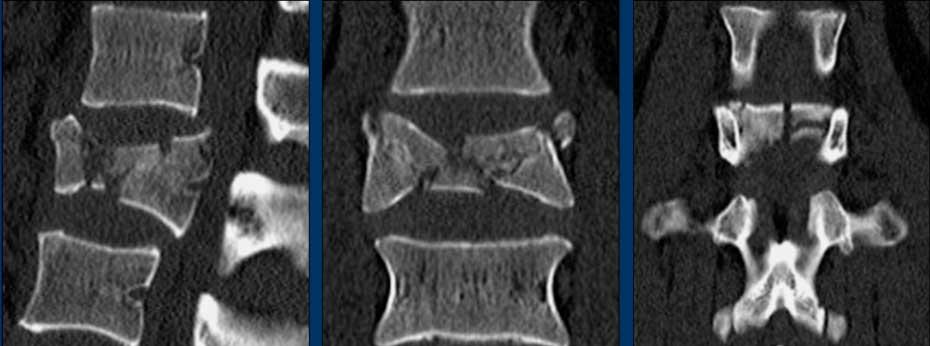

Type C Translational injuries

We start with the most severe injury and work from there.

Translational injuries are dislocation or displacement of a vertebral level from the level below or above.

There are no subtypes because various configurations are possible.

There is a high degree of instability and therefore an indication for surgery.

Images

Here we see a dislocation of the proximal levels to the right lateral side in the coronal plane.

Conclusion

Type C injury.